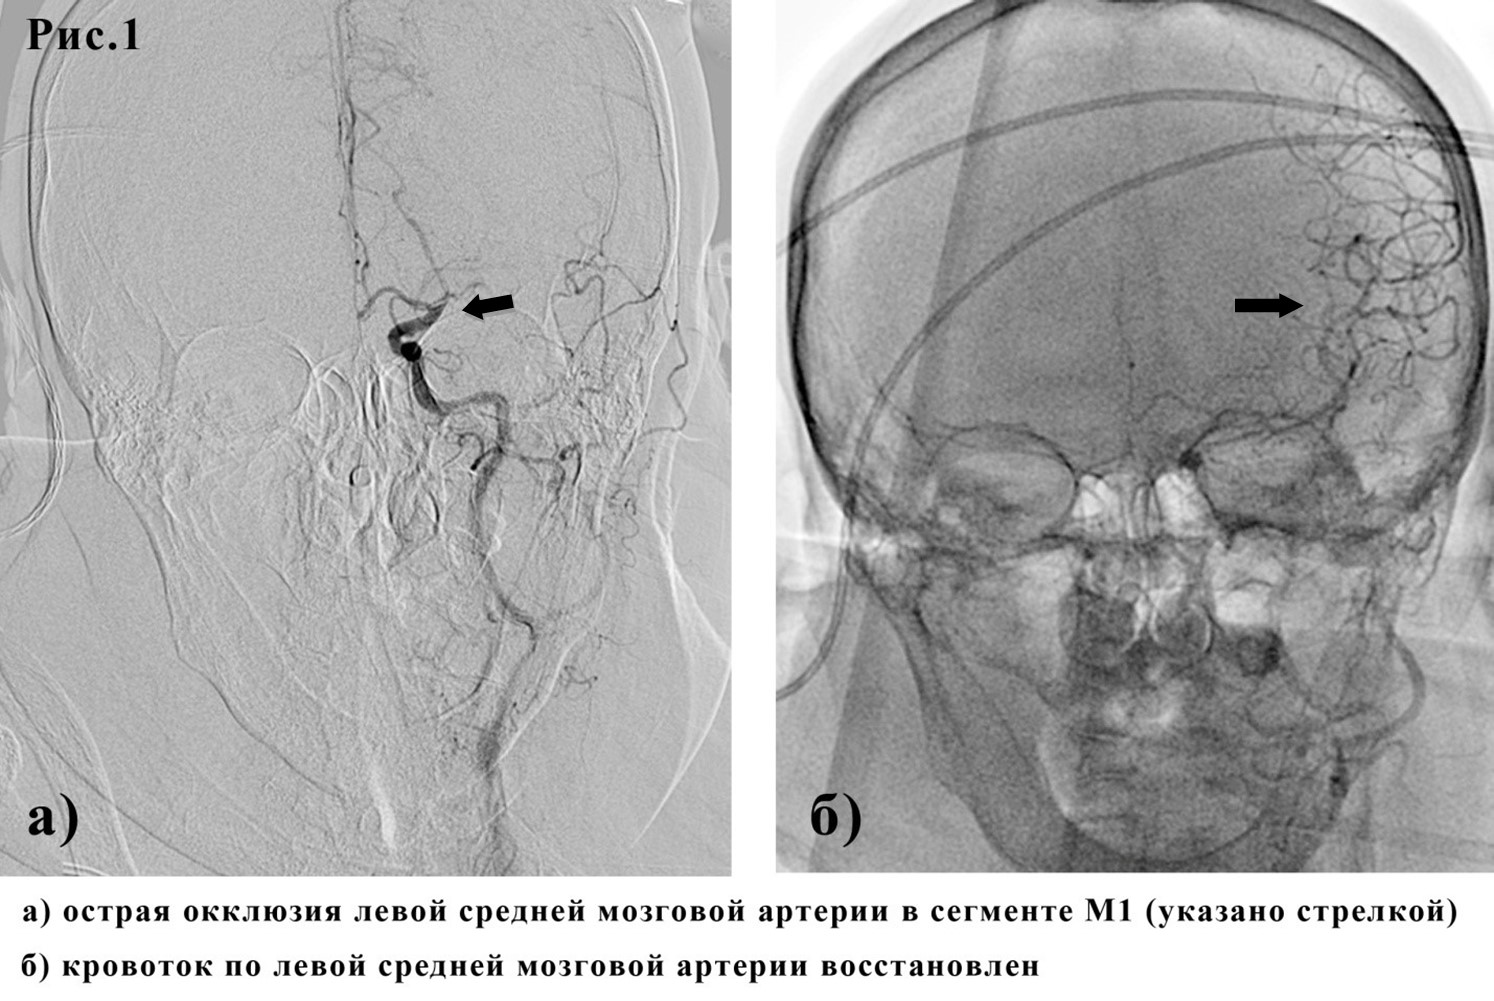

В 16:10 выполнена церебральная и коронарная ангиографии при которых определяется: 1) тромботическая окклюзия левой средней мозговой артерии в сегменте М1, кровоток TICI 0 (рис 1а). 2) тромботическая окклюзия ПМЖА в средней трети, кровоток TIMI 0 (рис 2б).

Первым этапом выполнена тромбоэкстракция при помощи стент-ретривера 4,0х20мм из левой средней мозговой артерии с использованием системы проксимальной защиты. Получен кровоток на уровне TICI 3 (рис.1б). Диссекций и паравазаций нет. Наблюдался выраженный регресс неврологической симптоматики сразу после восстановления кровотока по средней мозговой артерии: больная начала двигать правой рукой и ногой, говорить.